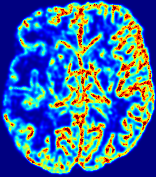

LesionRefer to captionRefer to captionRefer to captionRefer to captionRefer to captionRefer to caption𝐕rgbsubscript𝐕𝑟𝑔𝑏{\bf{V}}_{rgb}Refer to captionRefer to captionRefer to captionRefer to captionRefer to captionRefer to caption𝐕2subscriptnorm𝐕2{\|\bf{V}}\|_{2}Refer to captionRefer to captionRefer to captionRefer to captionRefer to captionRefer to captionRefer to caption3.53.53.52.82.82.82.12.12.11.41.41.40.70.70.70.00.00.0(mm/s)𝑚𝑚𝑠(mm/s)D𝐷DRefer to captionRefer to captionRefer to captionRefer to captionRefer to captionRefer to captionRefer to caption0.0200.0200.0200.0160.0160.0160.0120.0120.0120.0080.0080.0080.0040.0040.0040.0000.0000.000(mm2/s)𝑚superscript𝑚2𝑠(mm^{2}/s)Slice #1Slice #2Slice #3Slice #4Slice #5Slice #6

Figure 4: PIANO feature maps for another patient in the ISLES 2017 training set, where the lesion is located in the right hemisphere. Top row: segmented stroke lesion region (white) on different slices. The corresponding slices for the PIANO feature maps are shown in the following rows.

For a better insight into an estimated velocity field 𝐕𝐕{\bf{V}} and diffusion field 𝐃𝐃{\bf{D}}, we compute the following maps: (1) 𝐕rgbsubscript𝐕𝑟𝑔𝑏{\bf{V}}_{rgb}: Color-coded orientation map of 𝐕=(Vx,Vy,Vz)T𝐕superscriptsuperscript𝑉𝑥superscript𝑉𝑦superscript𝑉𝑧𝑇{\bf{V}}=(V^{x},V^{y},V^{z})^{T}, obtained by normalizing 𝐕𝐕{\bf{V}} to unit length and mapping its 3 components to red, green, blue respectively; (2) 𝐕2subscriptnorm𝐕2\|{\bf{V}}\|_{2}: 222 norm of 𝐕𝐕{\bf{V}}; (3) D𝐷D: scalar field in Eq. 5.

Fig. 3 and Fig. 4 show the PIANO feature maps estimated from two ISLES 2017 patients: all are highly consistent with the lesion in both cases. Details of the blood flow trajectories are revealed in 𝐕rgbsubscript𝐕𝑟𝑔𝑏{\bf{V}}_{rgb} by the ridged patterns and the sharp changes of colors in the unaffected (right) hemisphere, while the flat patterns appearing within the lesion provide little directional information about the velocity and indicate low velocity magnitudes. Velocity magnitudes are more directly visualized via 𝐕2subscriptnorm𝐕2\|{\bf{V}}\|_{2}, from which one can easily locate the lesion where 𝐕2subscriptnorm𝐕2\|{\bf{V}}\|_{2} is low. D𝐷D also indicates lower diffusion values in the lesion, though with less contrast potentially due to the fact that it captures the accumulated effect of CA diffusion at the voxel-level.